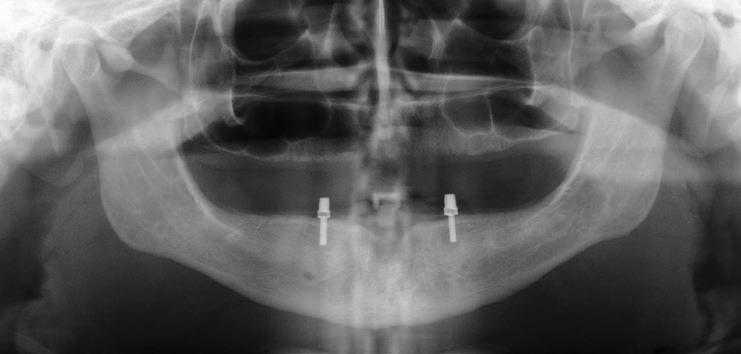

Implants were placed in areas of nos. 22 and 27. Implant no. 22 was Nobel Replace RP 4.3x11.5 torqued to 42.1 N/cm; implant no. 27 was Nobel Replace RP 4.3x11.5 torqued to 45.0 N/cm. Due to the patient wearing dentures, cover screws were placed and horizontal mattress sutures were placed. (The ends were clipped after the photos.) The patient was seen two days after and was healing well He was very happy with his treatment.